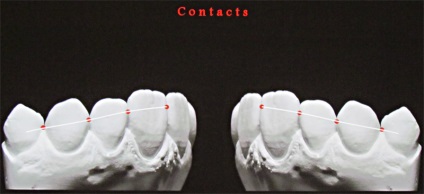

A frontális profilja az érintkező felületek az elülső fogak S-alakú, amely egy konvex rész és a konkáv rész.

A domború részét az érintkező felületek szintjén a legnagyobb szélessége a koronát képez két homlokegyenest kapcsolattartó pontok találhatók különböző magasságban. Két szomszédos érintkezési pontja két szomszédos fogak tartalmazhat egy kapcsolattartó pont, amelynek területe egyenlő a kb I mm-elülső fogak.

A konkáv része az érintkező felület biztosítja a sima átmenetet a fognyak, amelynek alakja közel van a henger. Ez a forma nyakuk meg egymástól megfelelő távolságban vágó stabilan lehet beállítani fogköztisztító ék, de ha a párhuzamosság törött nyakkal, így zsúfoltság, fogak lejtők, vagy sarkok, ék telepítés tolódik mélyen a fogak közötti résbe, ami a károsodás kockázata, hogy a fogak közötti szemölcsök.

Annak ellenére, hogy két szomszédos korona szemközti fogak különböző magasságú, a vele érintkező pont az érintkező felületek találhatók ugyanazon a szinten. Ez az eljárás biztosítja a fogazat különböző konvex medialis és laterális / távoli felületek. Fang, kivételt képeznek az egymást követő csökkenése a magassága a fogak korona, az integráció a fogsor által nyújtott speciális formája. Másrészt, a különböző domborulata az érintkező felületek a fogak vezet az a tény, hogy a korona a felső metszőfogak helyzetben laterális és mediális kapcsolattartó pontok különbözik függőlegesen körülbelül I mm oldalsó felületén - közelebb a nyakát a fogak, a mediális felszínén - közelebb áll az élvonalbeli .

Ennek eredményeként, az érintkezési pontok az elülső felső fogak vannak elrendezve egy ív, megismételve a helyzetben a vágóélek vagy meghajlítjuk a felső széle az alsó ajak. Az alábbiakban, mind a felső fogazat a kapcsolattartó pont a kettő között metszőfogak.

A kapcsolattartó pontok között, a felső elülső fogak elrendezve egy görbe mentén, megismételve a hajlam a vágóélek a felső és alsó ajak kontúr. Ha az érintkezési pont között a metszőfogak és a szemfogak vetített középvonalában, akkor hogy három szinten egy pályát körülbelül 1 mm.

Az átmenet az érintkező felületek az orális marginális gerincek képező felülete, alsó élei mentén a palatinális / lingvális fossa. Behajtott marginális gerincek megvédi fogköztisztító papillákban sérülésmentesen funkció még ha nem is nagyon szoros kapcsolati pontokat.